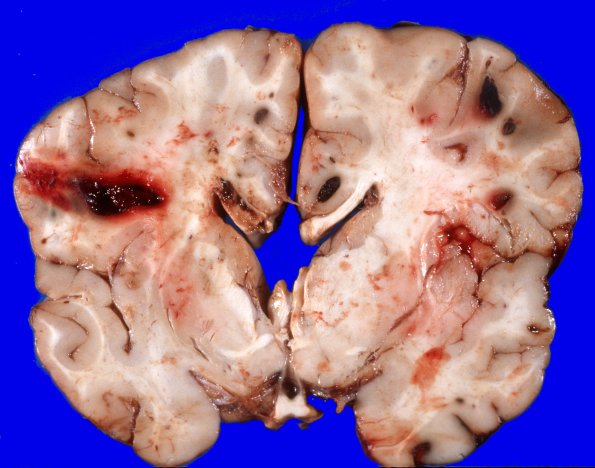

Washington University Experience | NEOPLASMS (HEMATOLYMPHOID) | Granulocytic Sarcoma | 4A3 Leukemic nodules (Case 4) gross 7

There is bilaterally symmetrical cerebral edema causing flattening of the gyri and narrowing of the sulci over both hemispheres. Cross sections of the bilateral cerebral hemispheres disclose multiple well circumscribed areas of hemorrhage, many at the cortical gray/white junction. These measure from approximately 1 mm to 2 cms in diameter. In some cases, the central portion of the hemorrhage appears to be made up of a pale appearing substance.